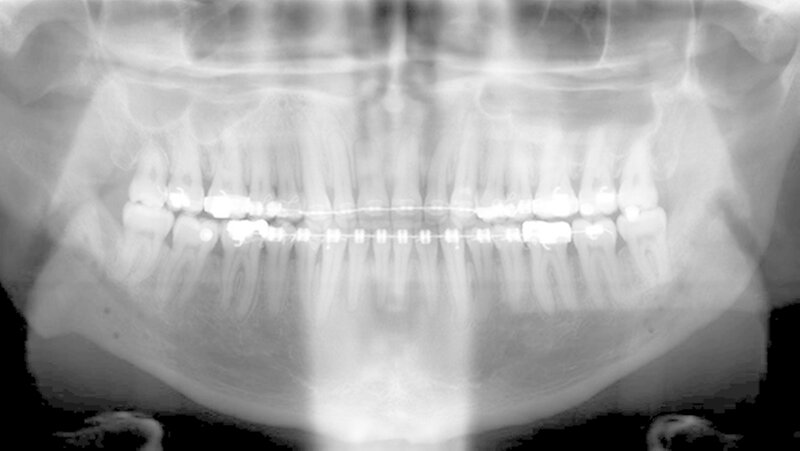

Der Patient stellte sich erstmals 2010 in der Stuttgarter MKG-Spezialsprechstunde vor. Im ersten Schritt wurde der Tumor an der Hirnanhangdrüse über die Nase entfernt. In interdisziplinärer Zusammenarbeit mit einem Fachzahnarzt für Kieferorthopädie wurden im ersten Behandlungsabschnitt die Zahnbögen ausgeformt. Um den Oberkiefer in der Breite zu dehnen, führten die Stuttgarter Zahnärzte im Oktober 2012 eine chirurgisch unterstützte Gaumennahterweiterung durch.

Nach dreidimensionaler Planung im zahntechnischen Labor, in dem die Bissschlüssel konventionell hergestellt wurden, wurden dann ein Jahr später beide Kiefer operativ mobilisiert. Hierzu wurde von einem Schnitt im Mund der Oberkieferknochen freigelegt.

Mit einer Säge wurde ein gezielter Knochenschnitt durchgeführt. Nach der Präparation wurde der zahntragende Abschnitt des Oberkiefers vom restlichen Gesichtsschädel gelöst. Erst wurde die Bisssituation anhand des Bissschlüssels exakt eingestellt, dann mit 2 mm dicken Osteosyntheseplatten aus Titan der Knochen in der neuen Position mithilfe von Titanschrauben fixiert.

Im Unterkiefer erfolgte dann die Schnittführung im Zahnfleisch hinter dem letzten Backenzahn beidseits. Nun wurde der Unterkiefer mit spezieller Technik durchtrennt um die zahntragende Basis vom gelenktragenden Knochenabschnitt des Unterkiefers zu verschieben. Bei der Präparationwurde der im Unterkieferknochen verlaufende Gefühlsnerv der Unterlippe sorgfältig geschont.

Die neue Position wurde mit einem zweiten Bissschlüssel, der die endgültige Bisssituation einstellt,zugeordnet und mit Osteosyntheseplatten und -schrauben gesichert. Die Operation ging mit einem stationären Aufenthalt von nur fünf Tagen einher.